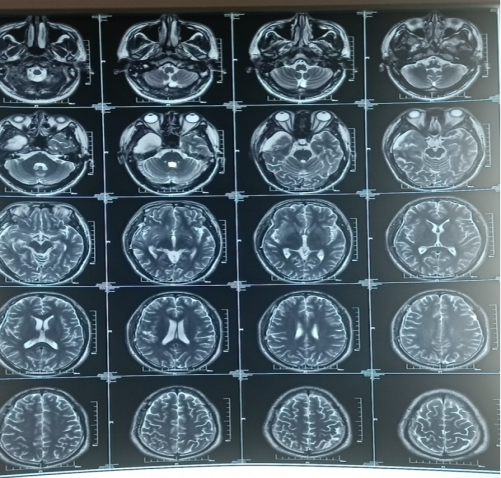

20190927郑大一附院:右侧颞叶巨大占位,考虑胶质瘤。